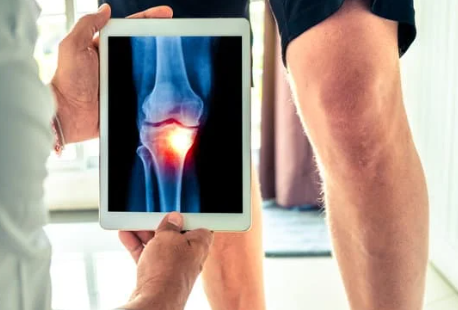

무릎 관절 통증의 증상

무릎 관절 통증의 증상은 개인에 따라 다를 수 있지만, 일반적으로 다음과 같은 증상이 나타납니다.

- 통증: 무릎 안팎에서 느껴지는 통증. 특히 움직일 때나 체중을 실을 때 더 심해질 수 있습니다.

- 부기: 무릎 부위의 부풀어 오름. 염증이나 부상으로 인해 발생할 수 있습니다.

- 운동 제한: 무릎의 움직임이 제한되거나 경직되는 느낌. 무릎을 구부리거나 펴기 어려울 수 있습니다.

- 소음: 운동할 때 무릎에서 소리가 나는 경우. 이는 관절 내의 연골 손상이나 마찰로 인해 발생할 수 있습니다.

무릎 관절 통증의 치료 방법

무릎 통증을 완화하고 치료하기 위해서는 다음과 같은 방법이 있습니다.